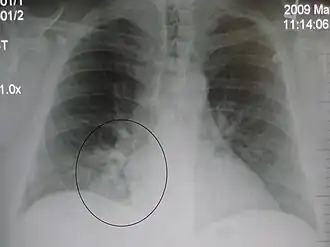

AP CXR showing pneumonia of the lingula of the left lung -

Right upper lobe pneumonia as marked by the circle. -